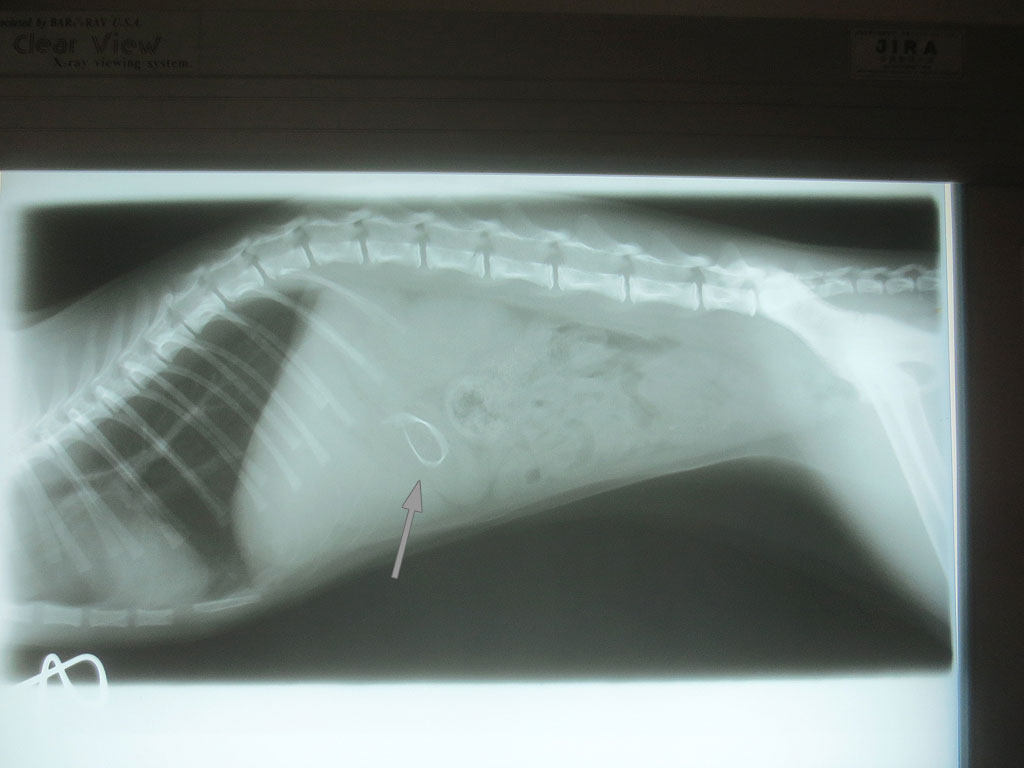

そして、レントゲンの現像も終わって、また診察室に呼ばれ、早速、レントゲンの写真を見せて頂いたのですが、いきなりですが、アビのすけの胃の中に異物が…。

紐とかだったらレントゲンに写らないそうなのですが、かなりはっきりと写っていて、何か、金属的なものを飲み込んでいるとの事…。

食パンの袋の口を結ぶ、芯に針金が入ったくるくるってひねって巻くやつの様だと先生はおっしゃったのですが、そんなものは部屋の中にはない筈なのですが、私が落としてしまったのかも知れず…。

全部で6枚、撮って頂いたのですが、後の5枚は、特に何も写っていなかったので、連続でアップさせて頂きます。

胃の中は空っぽだった様で、ご飯はやっぱり食べたかった様なのですが、固形の物は受け付けなくって、なので、朝の1回目ご飯も缶詰だけ食べて、カリカリは残していた様だし、ご飯を撒き散らかしていたのも、私がカリカリと缶詰を混ぜていたので、缶詰だけを食べようと思って振り払っていた結果、カリカリがばら撒かれてしまったのだと、やっと因果関係の筋が通ったので、私的には納得。

でも、この異物がお尻から出て行かなかったら、手術をしなければならないとの事で、こんな針金みたいのは腸を通る訳もないだろうから、手術をしなければいけない可能性が大との事で、子猫のアビのすけに手術をさせてしまうなんて、本当に申し訳なくて…。